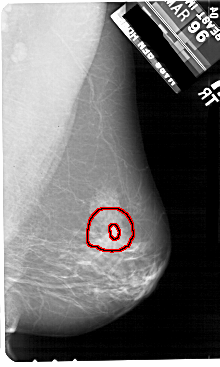

A_1908_1.RIGHT_MLO

LEFT_MLO LINES 5491 PIXELS_PER_LINE 3511 BITS_PER_PIXEL 12 RESOLUTION 43.5 NON_OVERLAY

RIGHT_MLO LINES 5491 PIXELS_PER_LINE 3286 BITS_PER_PIXEL 12 RESOLUTION 43.5 OVERLAY

FILE: A_1908_1.RIGHT_MLO.OVERLAY

TOTAL_ABNORMALITIES 1

ABNORMALITY 1

LESION_TYPE MASS SHAPE IRREGULAR MARGINS SPICULATED

ASSESSMENT 5

SUBTLETY 4

PATHOLOGY MALIGNANT

TOTAL_OUTLINES 2

BOUNDARY

CORE